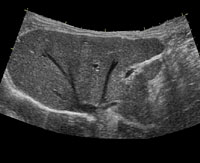

腹部エコー(肝臓)